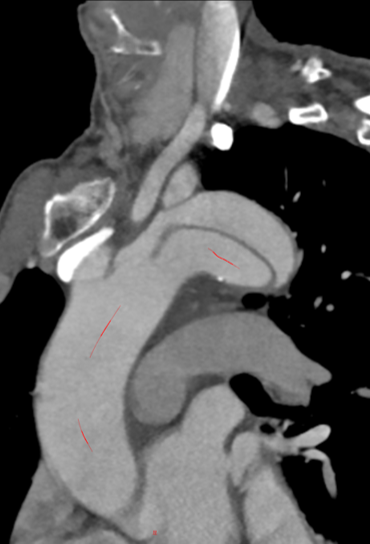

术后12个月CT血管造影(CTA)随访显示,支架移植物位置稳定,无明显移位或变形,分支血管通畅。

First-In-HuMan study--CTA

CTA 12 monthes FU